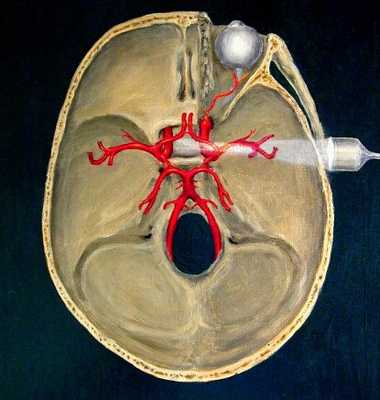

- транскраниальное дуплексное сканирование, с помощью которого можно визуализировать артерии головы - передние, средние, задние, базиллярную, внутричерепные сегменты позвоночных. У 10-20 % пациентов выполнить процедуру невозможно в связи с плохой проницаемостью костей черепа для УЗ- волн.

Лимфатическая система (схематично)